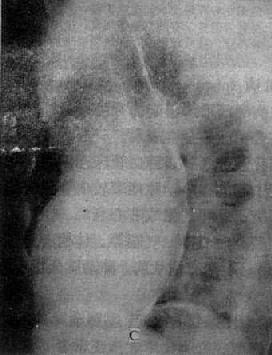

图3-2-15 二尖瓣狭窄

A.右前斜位:右心室增大,肺动脉段突出(↑),心前间隙变窄(↑),左心房轻度增大;B.后前位:心增大,呈二尖瓣型,右心室增大,肺动脉段突出,左心耳增大,出现第三弓(↓),有肺瘀血表现;C.左前斜位:右心室增大,左心房增大不明显;左心室不增大。